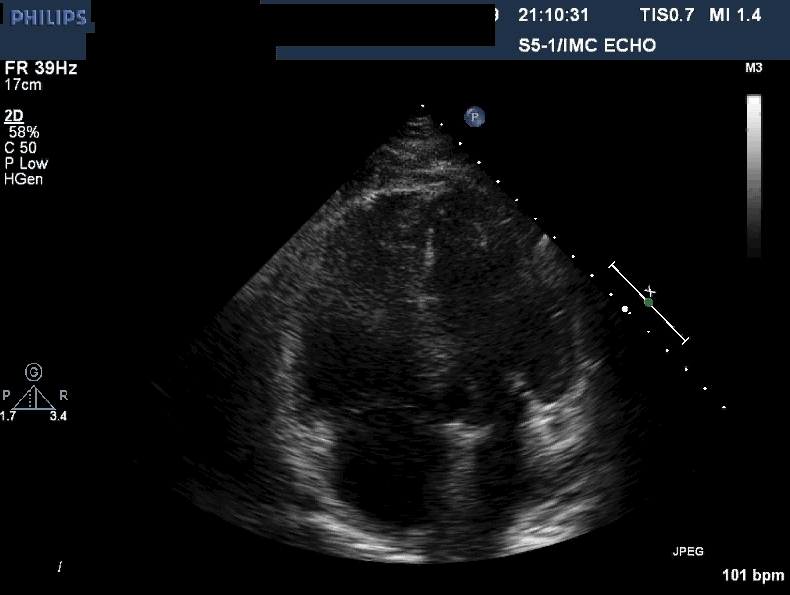

Acute pulmonary embolism.

The echocardiogram shows an apical, four-chamber view. This patient

has a hyperdynamic, underfilled left ventricle (the chamber on the upper

right), and an enlarged right ventricle (chamber on the upper left).

The right ventricle is globally hypokinetic, with the exception of the

apex, which is hyperkinetic . This hyperkinetic apex is sometimes

referred to as an apical wink. This echocardiographic finding

(hypokinesia/akinesia in the mid-free right ventricular wall with

preserved apical kinesis) is commonly called McConnell’s sign.1